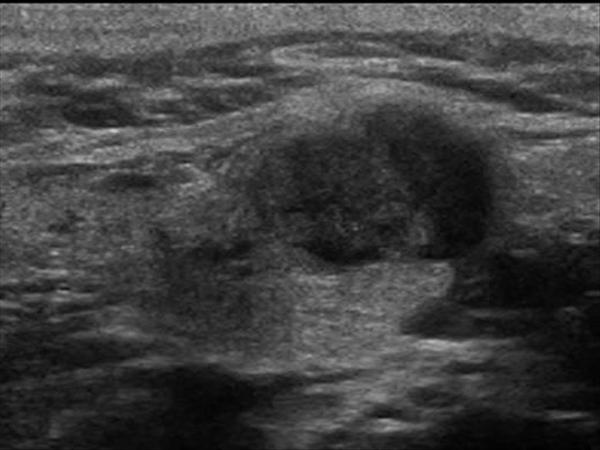

U tuyến nước bọt

» Thông tin: Nữ giới – 60 tuổi.

» Lâm sàng: Khối vùng góc hàm.

# Di căn tuyến nước bọt dưới hàm.